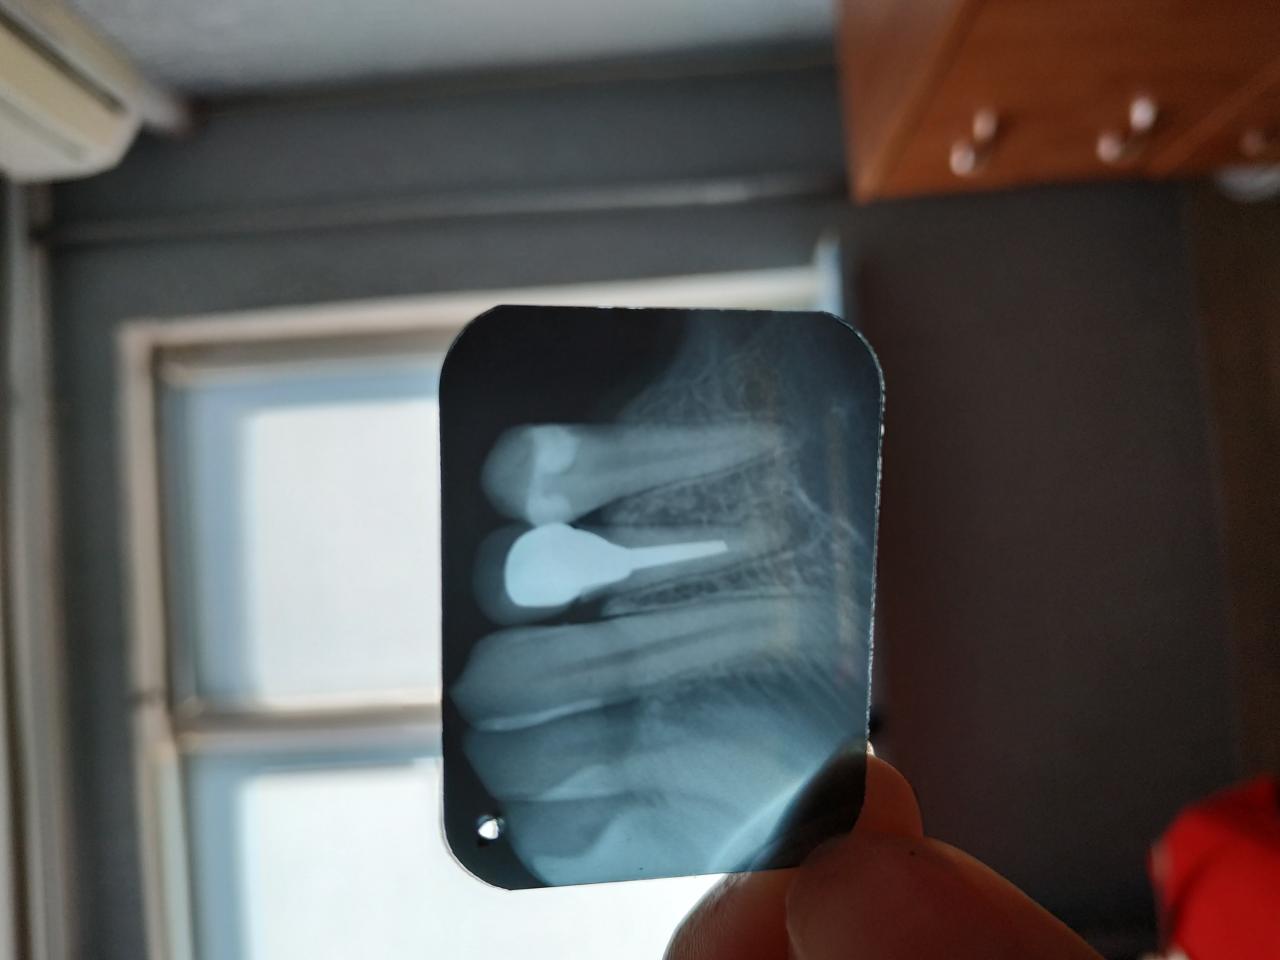

Добрый день. Можно ли спасти зуб? 4-ка снизу.Меньше года назад поставили коронку на вкладку

. Последние два месяца зуб болит периодически. Врач сказал,что штифт глубоко и под ним гранулёма. Только удалять. Но у меня и так уже 5 зубов нет. Одного так же лишилась через полгода после установки коронки. Теперь даже боюсь мосты ставить,чтоб не лишится ещеВложение 13129876 4-х зубов.....

Клиническая ситуация довольно стандартная. Изначально - некачественное лечение канала. А дальше уже не имеет значения, на сколько красивая и дорогая коронка, результат - переделывание с потерей очередных средств, времени и нервов.

Если канал лечился давно (5 лет и более), то врач, ставивший коронку, не мог не заметить гранулему, а снимок зуба он точно должен был сделать. В данной ситуации хроническому течению процесса "благоприятствует" временной фактор, тогда кистэктомия с резекцией верхушки корня будет с наибольшим процентом положительным решением.

Снимок показывает, что вкладку сделали с правильной длиной ножки. Но, если стоит вопрос об удалении зуба, всегда можно попробовать извлечь вкладку (бывает, фиксируют на "плохой цемент", вкладка имеет плохое прилегание к зубу с большими зазорами и пр.). Если вкладка извлекается, тогда есть возможность перелечить канал, и хирургия, вряд ли, понадобится.

PS: А ставить мост бояться не стоит, если он делается по показаниям, и зубы под ним готовятся качественно.